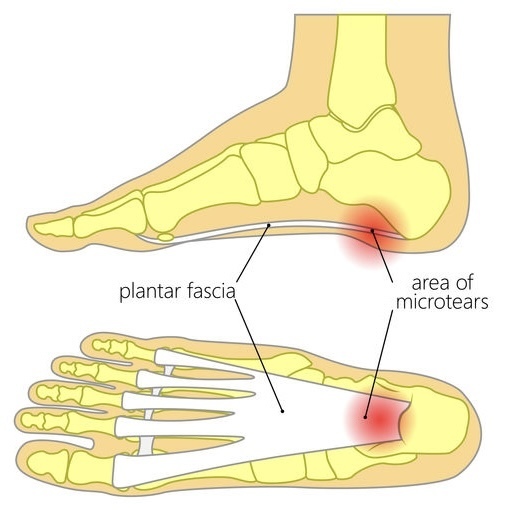

足底腱膜炎

①足底腱膜(実質部)

足の指の付け根から踵(かかと)に伸びる腱の膜状な組織

②足底腱膜(踵骨付着部)

足底腱膜と踵を結ぶ部分

③踵骨

かかとの骨

④踵骨下脂肪体

踵に下に存在する柔らかい組織

①足底腱膜は、足が体重を支えている時に張力を受ける組織として機能することで足のアーチの支持に関係しています。また足趾(足のゆび)を反らすと足底腱膜が緊張するため、歩行時の推進力としても機能します。つまり体重がかかった際の衝撃吸収の役目や歩行時に機能が発揮されているため、スポーツにおける長時間走行や仕事における長時間立位などで②付着部が炎症になります。

④踵骨下脂肪体はかかとの骨の下にある脂肪組織で衝撃吸収のクッションの役割をしています。足底腱膜やアキレス腱と連結しており、それらの硬さによって緊張されると、正常な圧縮反応が働かず、衝撃吸収ができなくなります。

上記の構造で衝撃吸収がうまく果たされないと、③踵骨自体が炎症し痛みを生じる病態にまで至ることもあります。